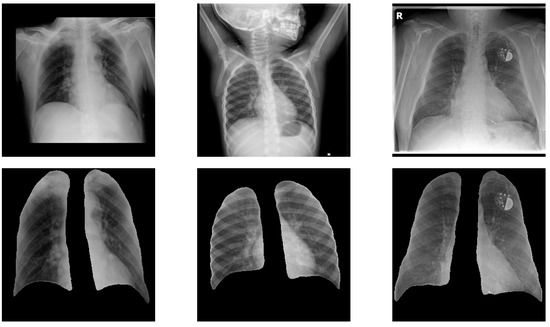

The recent Coronavirus Disease 2019 (COVID-19) pandemic has put a tremendous burden on global health systems. Medical practitioners are under great pressure for reliable screening of suspected cases employing adjunct diagnostic tools to standard point-of-care testing methodology. Chest X-rays (CXRs) are appearing as [...] Read more.

The recent Coronavirus Disease 2019 (COVID-19) pandemic has put a tremendous burden on global health systems. Medical practitioners are under great pressure for reliable screening of suspected cases employing adjunct diagnostic tools to standard point-of-care testing methodology. Chest X-rays (CXRs) are appearing as a prospective diagnostic tool with easy-to-acquire, low-cost and less cross-contamination risk features. Artificial intelligence (AI)-attributed CXR evaluation has shown great potential for distinguishing COVID-19-induced pneumonia from other associated clinical instances. However, one of the associated challenges with diagnostic imaging-based modeling is incorrect feature attribution, which leads the model to learn misguiding disease patterns, causing wrong predictions. Here, we demonstrate an effective deep learning-based methodology to mitigate the problem, thereby allowing the classification algorithm to learn from relevant features. The proposed deep-learning framework consists of an ensemble of convolutional neural network (CNN) models focusing on both global and local pathological features from CXR lung images, while the latter is extracted using a multi-instance learning scheme and a local attention mechanism. An inspection of a series of backbone CNN models using global and local features, and an ensemble of both features, trained from high-quality CXR images of 1311 patients, further augmented for achieving the symmetry in class distribution, to localize lung pathological features followed by the classification of COVID-19 and other related pneumonia, shows that a DenseNet161 architecture outperforms all other models, as evaluated on an independent test set of 159 patients with confirmed cases. Specifically, an ensemble of DenseNet161 models with global and local attention-based features achieve an average balanced accuracy of 91.2%, average precision of 92.4%, and F1-score of 91.9% in a multi-label classification framework comprising COVID-19, pneumonia, and control classes. The DenseNet161 ensembles were also found to be statistically significant from all other models in a comprehensive statistical analysis. The current study demonstrated that the proposed deep learning-based algorithm can accurately identify the COVID-19-related pneumonia in CXR images, along with differentiating non-COVID-19-associated pneumonia with high specificity, by effectively alleviating the incorrect feature attribution problem, and exploiting an enhanced feature descriptor. Full article